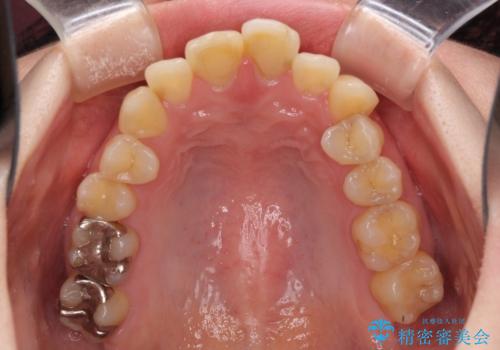

上下前歯のデコボコをきれいに インビザラインによる矯正治療

- 前歯の著しい叢生と前突感を気にして来院された患者様です。

叢生が強いため、事前に前歯をワイヤー矯正で速やかに叢生を解消し、その後はインビザラインにて矯正治療を行うこととしました。

ワイヤー矯正を併用したことで前歯の叢生を速やかに解消することができました。

一方口元の突出感を改善するために時間がかかり、2年超を要しましたが、満足のいく仕上がりとなりました。